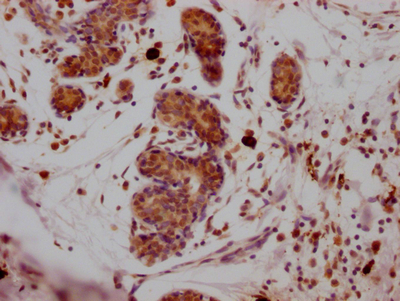

• IHC image of CSB-RA159561A0HU diluted at 1:100 and staining in paraffin-embedded human breast cancer performed on a Leica BondTM system. After dewaxing and hydration, antigen retrieval was mediated by high pressure in a citrate buffer (pH 6.0). Section was blocked with 10% normal goat serum 30min at RT. Then primary antibody (1% BSA) was incubated at 4℃ overnight. The primary is detected by a Goat anti-rabbit IgG polymer labeled by HRP and visualized using 0.05% DAB.